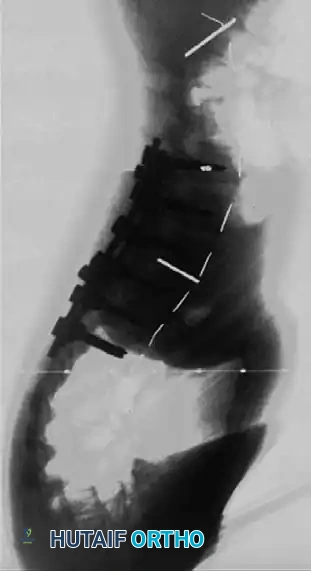

Following a wide posterior release (including complete facetectomies and removal of the ligamentum flavum), the spine is instrumented with pedicle screws and a 5.0-mm or 5.5-mm rod system.

* Advantages: This technique allows the surgeon to fuse the exact same number of levels as an anterior approach while entirely avoiding the morbidity of thoracotomy or retroperitoneal dissection.

* Outcomes: It provides excellent, rigid correction of both coronal and sagittal deformities, allowing for the restoration of physiological lumbar lordosis through posterior compression.